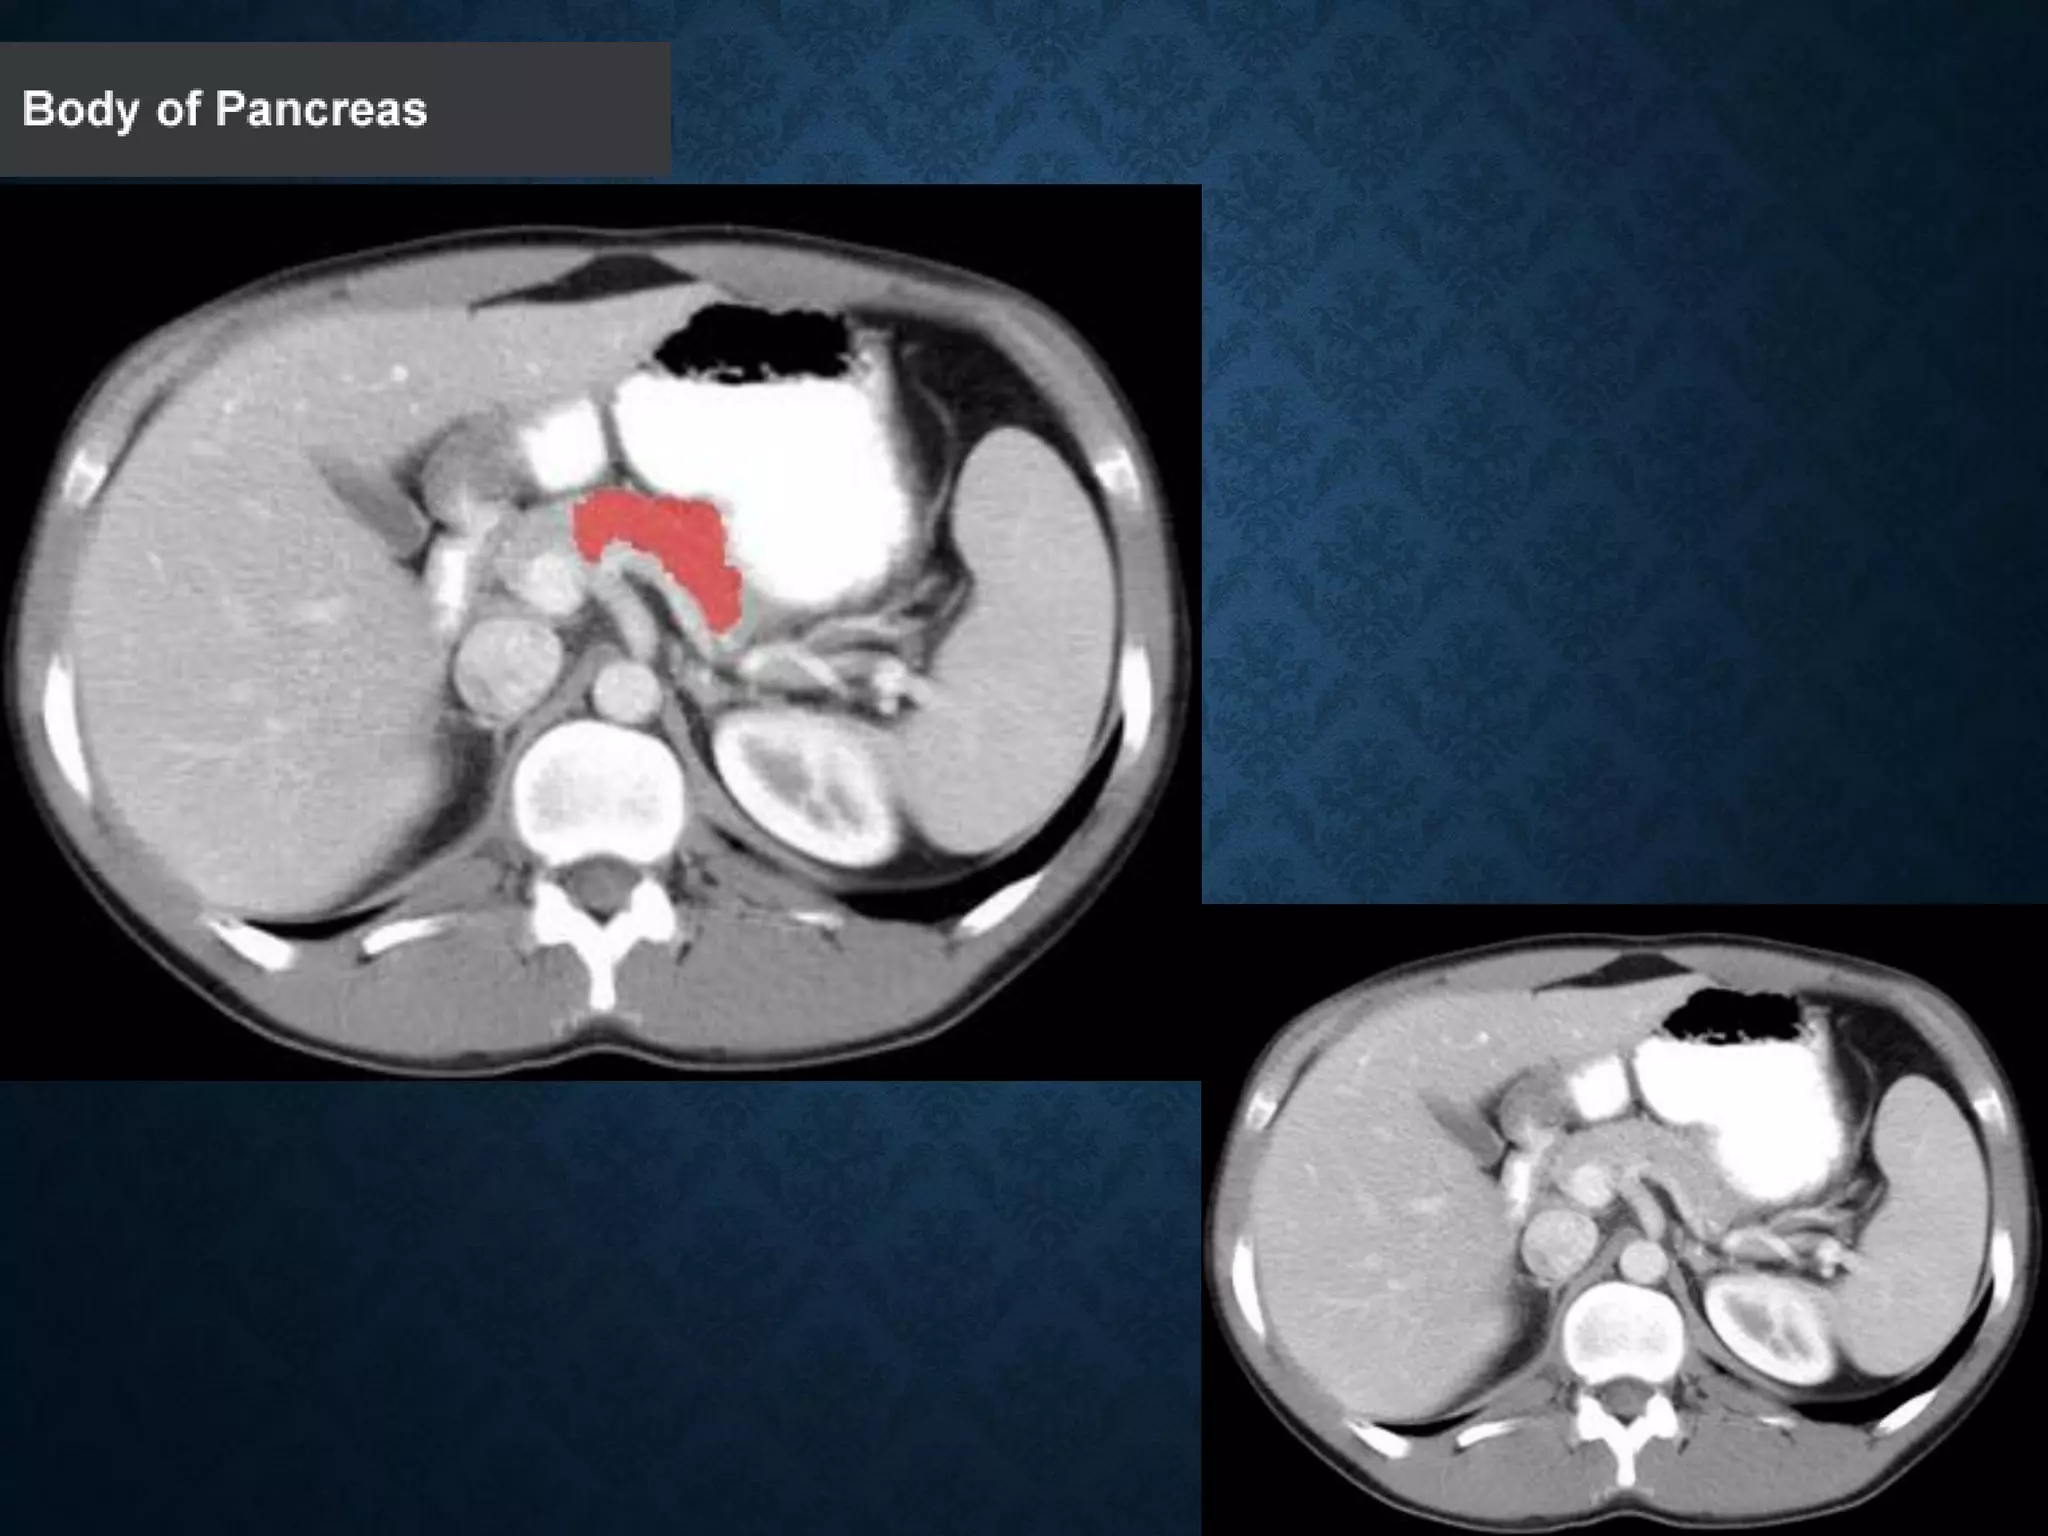

PANCREAS

1: Head of pancreas

2: Uncinate process of pancreas

3: Pancreatic notch

4: Body of pancreas

5: Anterior surface of pancreas

6: Inferior surface of pancreas

7: Superior margin of pancreas

8: Anterior margin of pancreas

9: Inferior margin of pancreas

10: Omental tuber

11:Tail of pancreas

12: Duodenum

PANCREAS 1: Head ofpancreas 2: Uncinate process of pancreas 3: Pancreatic notch 4: Body of pancreas 5: Anterior surface of pancreas 6: Inferior surface of pancreas 7: Superior margin of pancreas 8: Anterior margin of pancreas 9: Inferior margin of pancreas 10: Omental tuber 11:Tail of pancreas 12: Duodenum